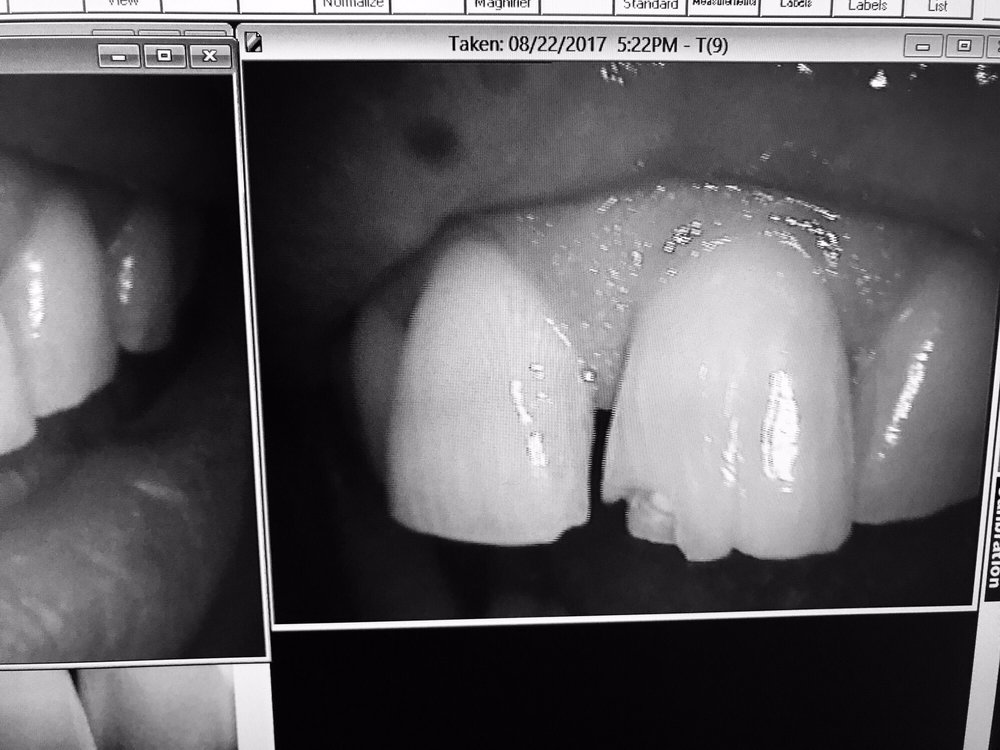

Photos for Imagine Advanced Dental Arts Yelp From yelp.com